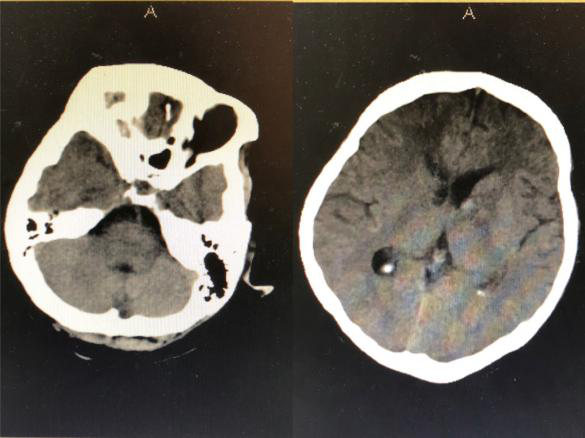

2018年9月3日,一位突发昏迷的患者被推到了神经外科病区。头颅CT提示脑出血破入脑室,合并急性脑积水,必须立即手术。当医生和患者家属提到手术时候,患者家属确实欲言又止,犹豫不决,询问患者家属后得知患者父母已故,也没有子女,唯一的亲人就是姐姐,患者与姐姐都没有工作,仅靠着姐姐的低保维持生活,如今听到要手术,姐姐不知如何是好。时间不等人,如果再拖延时间患者可能因急性脑积水失去生命,神经外科王刚副主任告诉患者家属先做手术抢救生命,钱以后再说,手术顺利进行,术后患者转入重症监护室。